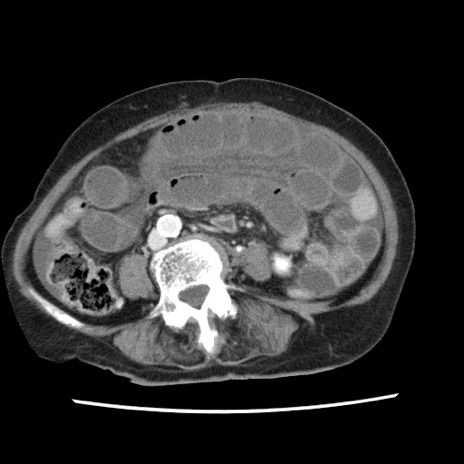

症例1(横断像)

【症例】80歳代女性

【主訴】腹痛

【現病歴】8時間前から腹痛あり来院。

【既往歴】糖尿病、脂質異常症、子宮体癌にて子宮全摘術

【身体所見】意識清明・会話良好だが腹痛で苦悶様、全腹部にわたって反跳痛と圧痛あり

【データ】WBC 13600、CRP 0.14、LDH 224、CK 90